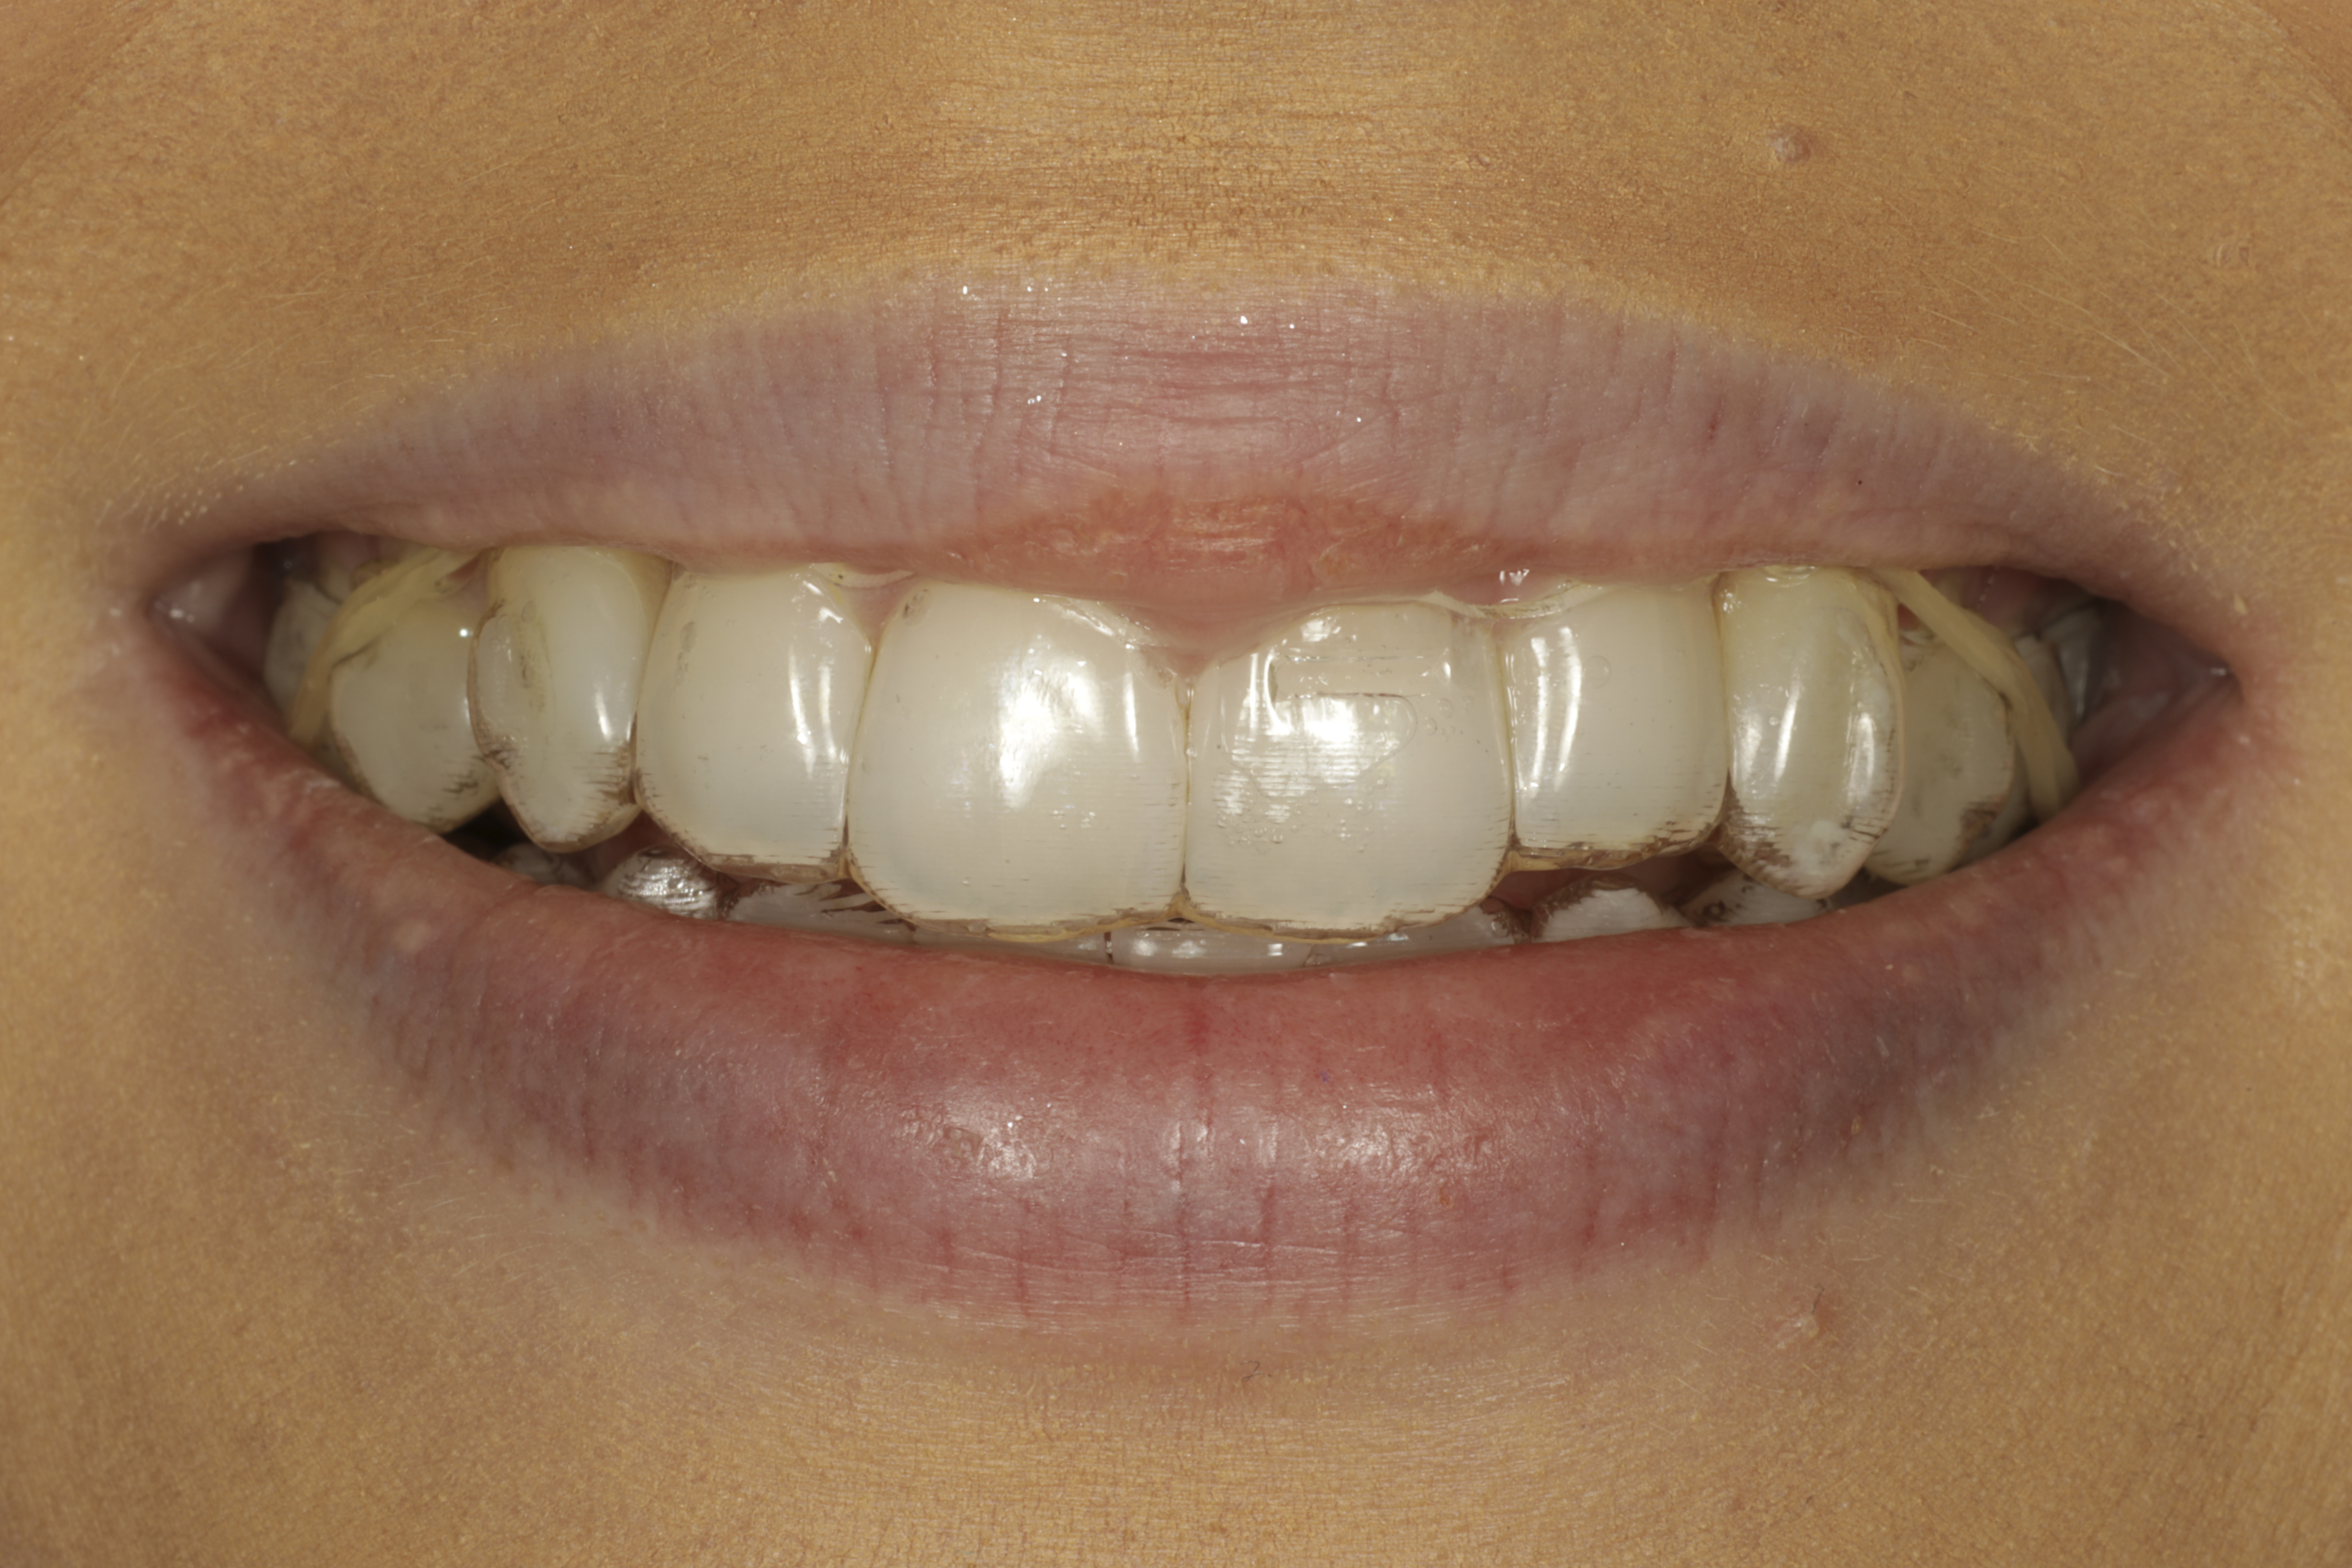

Alla suorittamiani hoitoja ja esimerkkejä siitä minkälaisia purentavirheitä voi korjata.

18kk hoito (Comprehensive). Keraamiset kuoret keskimmäisiin yläetuhampaisiin, kerrostusmuoveilla tehty reunimmaiset yläetuhampaat.